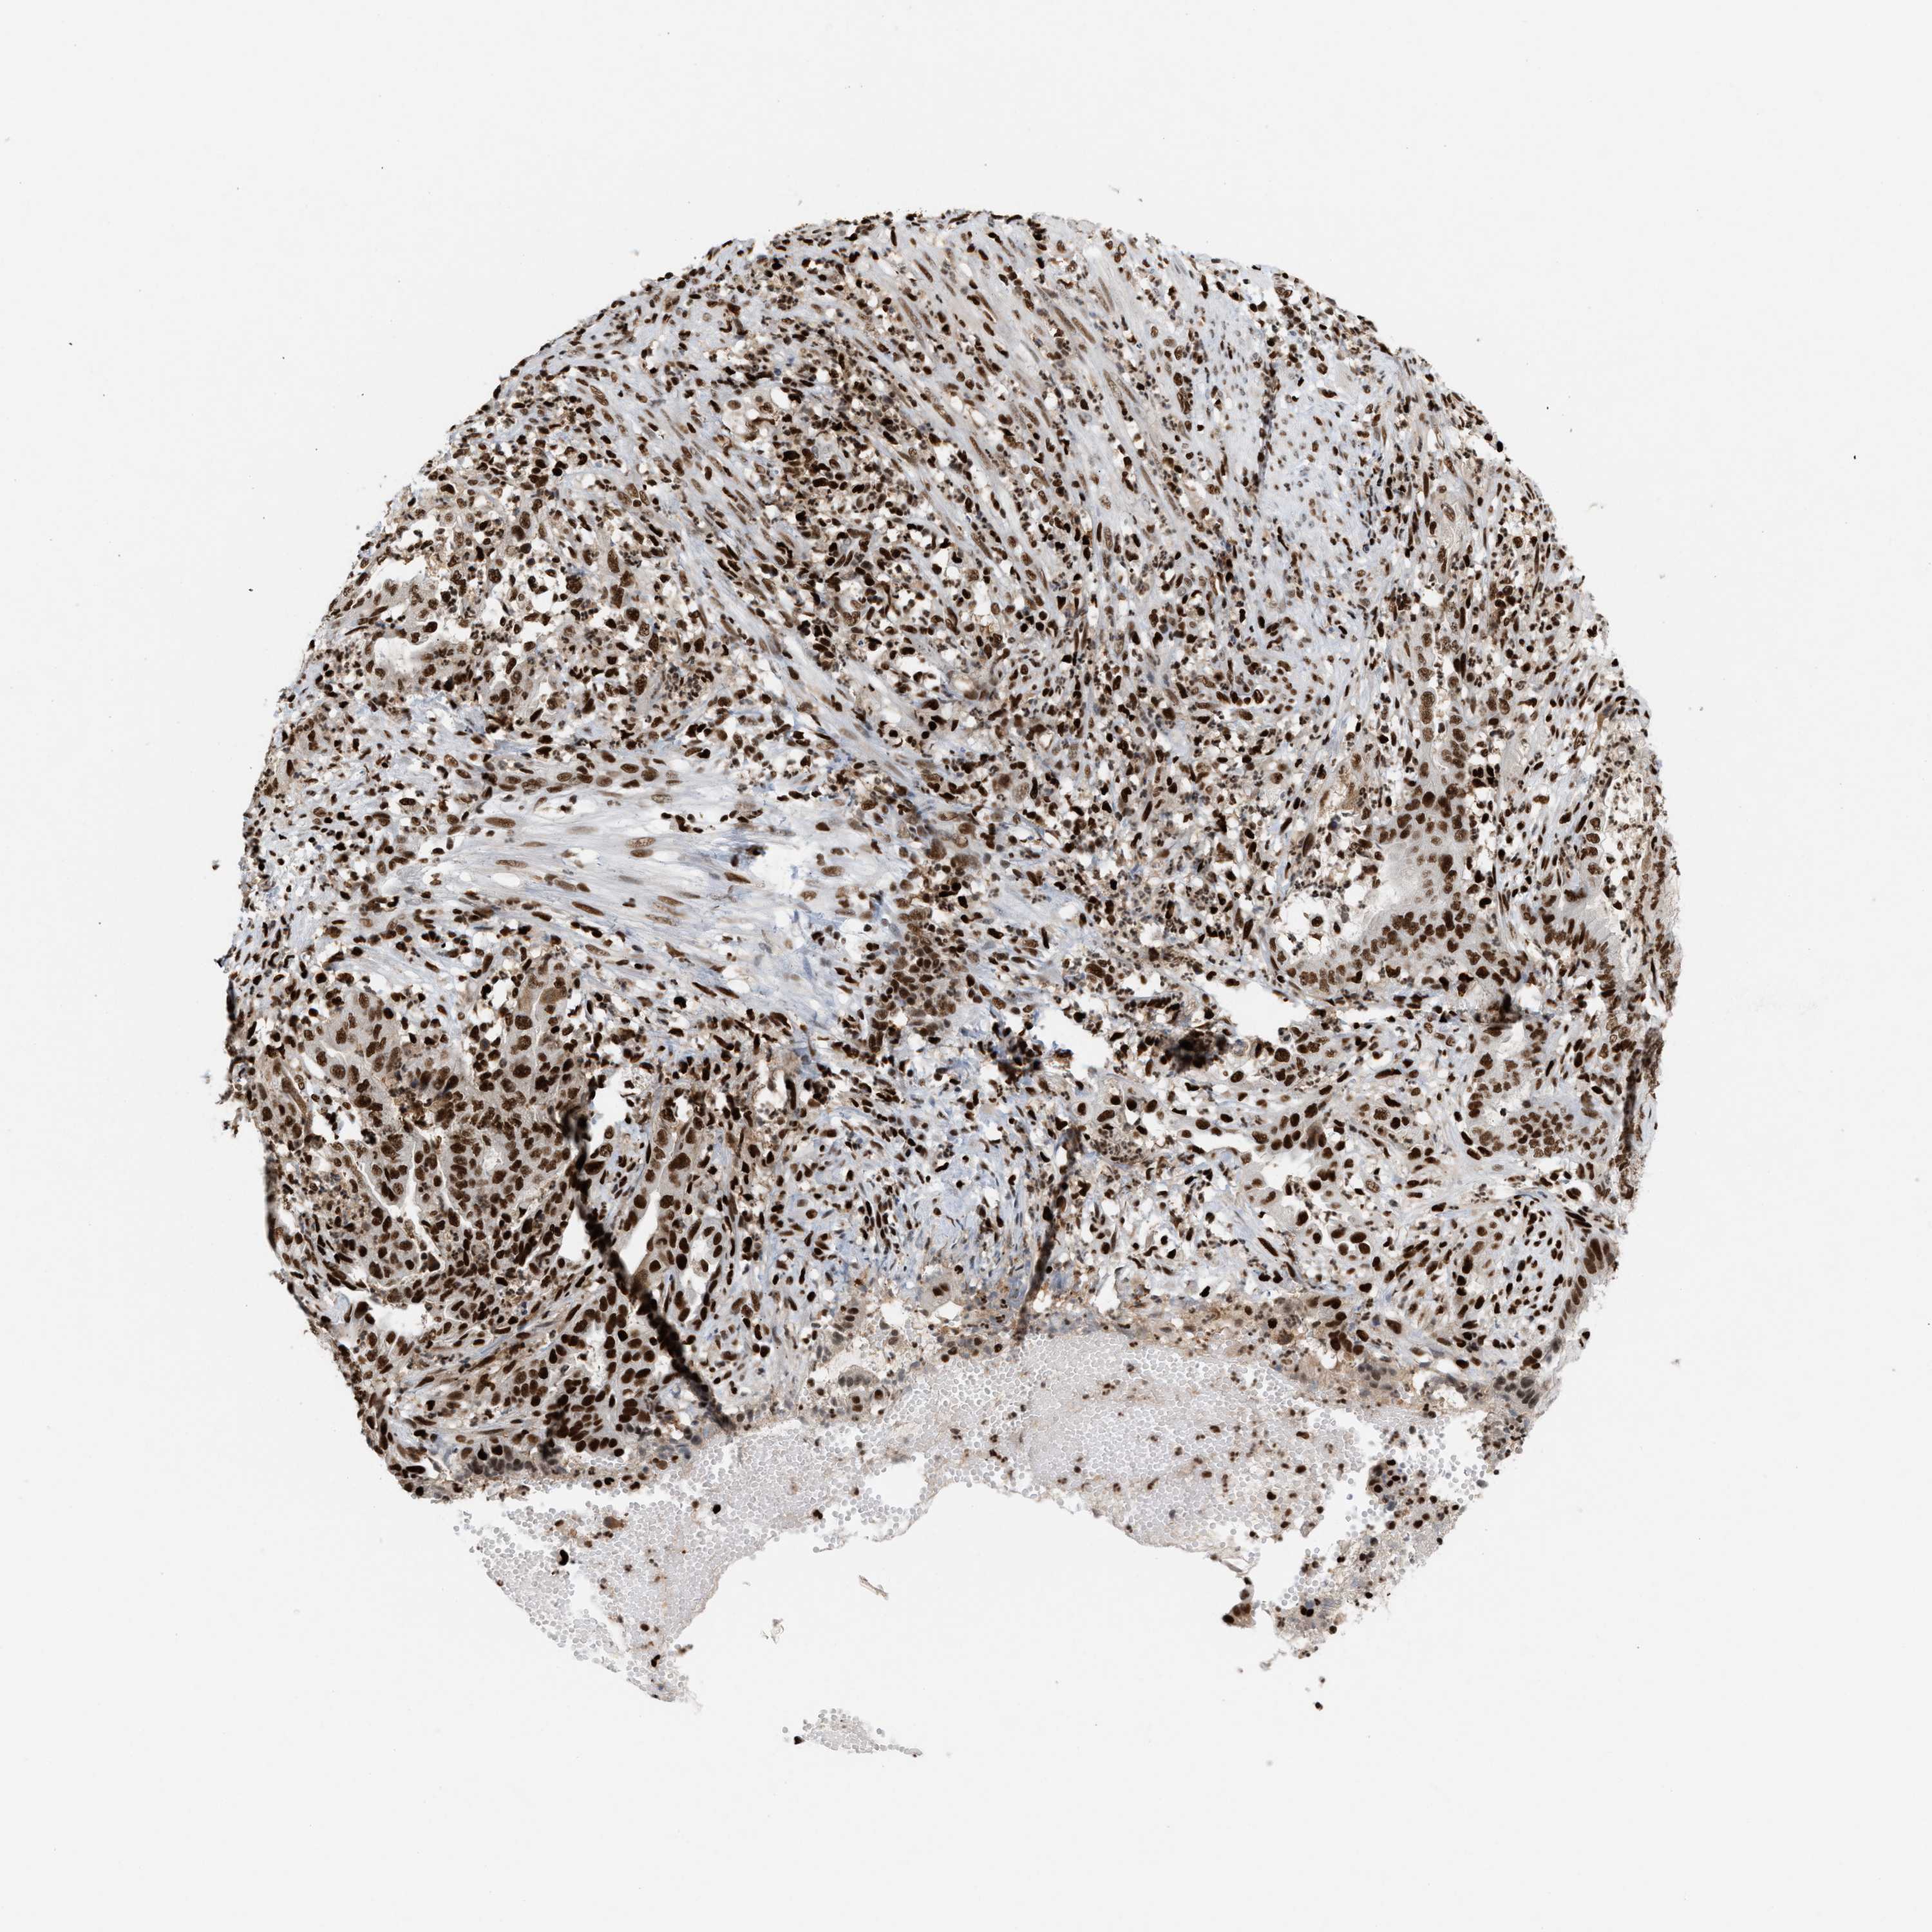

ENDOMETRIAL CANCER - Protein expressioni

A mouse-over function shows sample information and annotation data. Click on an image to view it in a full screen mode. Samples can be filtered based on level of antibody staining by selecting one or several of the following categories: high, medium, low and not detected. The assay and annotation is described here.

Note that samples used for immunohistochemistry by the Human Protein Atlas do not correspond to samples in the TCGA dataset.

Antibody stainingi

Antibody staining in the annotated cell types in the current human tissue is reported as not detected, low, medium, or high, based on conventional immunohistochemistry profiling in selected tissues. This score is based on the combination of the staining intensity and fraction of stained cells.

Each image is clickable and will lead to virtual microscopy that enables deeper exploration of all samples and also displays staining intensity scores, fraction scores and subcellular localization as well as patient and tissue information for each sample.

Antibody HPA022961

Antibody HPA024457

Staining

High

Medium

Low

Not detected

Intensity

Strong

Moderate

Weak

Negative

Quantity

>75%

75%-25%

<25%

None

Location

Nuclear

Cytoplasmic/membranous

Cytoplasmic/membranous,nuclear

Adenocarcinoma, NOS

Adenoma, NOS